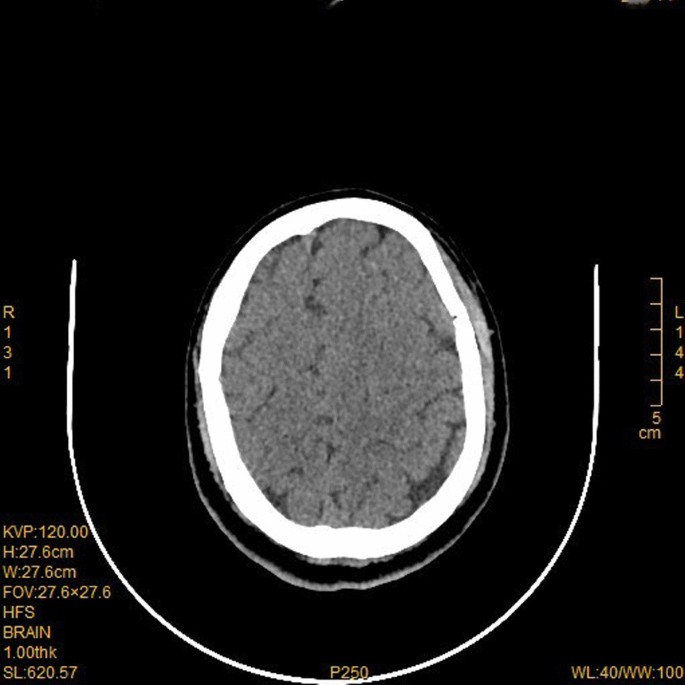

General anesthesia was induced and maintained according to standard protocols during surgical preparation. Then right pneumonectomy was performed, and the surgical incision was located at the posterolateral side of the fourth intercostal space. The pulmonary artery, pulmonary vein and bronchus were cut off with a stapler, with intraoperative bleeding of about 100 ml. After the operation, the thoracic drainage tube was clamped, and the patient returned to the ward after waking up. Three hours after the operation was completed, the patient suddenly lost consciousness while sitting in bed chatting with his wife. The patient’s blood pressure was low (76/53 mmHg), and the indexes of heart rate, respiration and oxygen saturation were normal. After opening the thoracic drainage tube, a small amount of tension gas and 200 ml of bloody fluid was discharged. We immediately performed CT examination and excluded brain lesions. CT examination showed that there was a large amount of gas in the tissue space between the chest and neck (Fig. 2). Blood clots accumulated in the thoracic cavity, and CT angiography showed no abnormalities in the major cerebral arteries (Fig. 3). However, multiple free air can be seen in the blood vessels of bilateral frontal sulcus (Fig. 4). In addition to free air, suspicious cerebral infarction was also seen in the right occipital lobe (Fig. 5). It is presumed that air entering the cerebral circulation led to air embolism. The patient had seizures soon after the CT scan, manifesting as binocular gaze and tremor of limbs. Then the patient was quickly transferred to ICU. Respiratory assistance, mannitol dehydration and empiric antibiotic treatment were used after ICU transfer. 800 ml pleural fluid was drained from the thoracic cavity 6 h after the operation, and a second thoracotomy was performed to stop bleeding. Then blood clot was removed from the thoracic cavity. After the operation, the patient was sent back to the ICU for ventilator-assisted breathing, and the head was protected by mild hypothermia using an ice blanket to prevent excessive brain damage. At the same time, mannitol dehydration was used to reduce brain edema and anti-infection treatment was carried out. On the next day, the brain CT showed a significant decrease of air in the brain (Fig. 6). There was no significant increase in cerebral infarction lesions compared with the first day. After 3 days of ventilator-assisted breathing, the patient’s condition gradually improved. On the third day after air embolism, the brain CT was reexamined. There were patchy low density areas in bilateral thalamic basal ganglia, temporal lobe and occipital lobe, which was cerebral infarction lesions. The patient was discharged after 25 days of treatment after cerebral infarction. He was conscious at the time of discharge, with neurological impairment symptoms of bilateral in which symptoms of left limb are more serious. The process from onset to recovery was smooth. After 3 months of follow-up, most of the neurological deficit symptoms had been recovered except for the left upper limb (Fig. 7).

Oxygen should be provided to patients to the maximum extent after CAE, which can reduce the volume of gas emboli. Hyperbaric oxygen therapy was reported to be an effective method in promoting the prognosis of CAE [8, 11,12,13]. Our patient had no respiratory failure symptoms after CAE, but we still used ventilator to assist breathing for 3 days, which should be an effective way to provide sufficient oxygen to the patient’s brain. Reexamination of CT results the next day demonstrated a significant reduction of air in the cerebral circulation. Patients’ outcome after air emboli can be variable and may depend on initial presentation. In one series of patients presenting with air emboli, 50% of patients presenting without encephalopathy had good or complete recovery while only 29% of patients presenting with encephalopathy had good recovery [14].